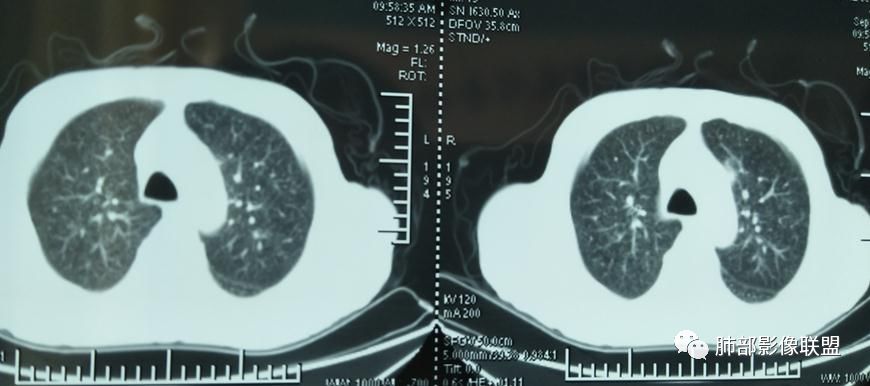

2019-10-20复查CT如下:

两肺弥漫性粟粒样结节伴左上肺小结节,呈三均匀分布,有结核的临床表现,支持血性播散性肺结核。

大小、分布均匀,边缘清楚

细小结节,弥漫,撒米粒样——血道来源

部分可见分支状

边缘稍平直

毛刺细弱

还是支持结核

血道来源的病灶,均匀、细微,而且部分有分支状,都符合粟粒型肺结核

10月20日的CT其实是抗痨治疗近1月复查的CT。患者来我院后抗痨治疗体温下降,症状明显好转。

急性血行播散型肺结核  两肺广泛分布粟粒大小的结节状密度增高影,具有大小均匀、分布均匀、密度均匀的典型“三均匀”特征,注意急性血播病灶非常小,一般粟粒影直径1~2mm。

病灶密集者出现肺外围血管影不清或减少。